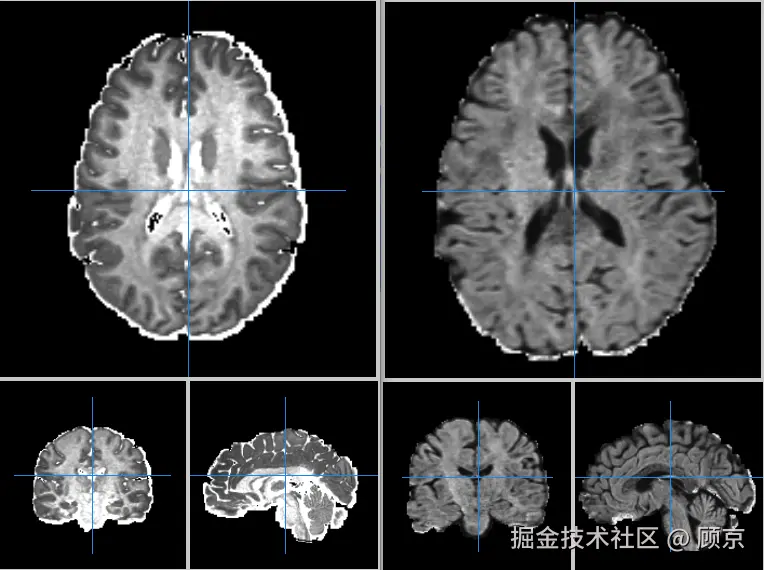

Mango

Mango, (Multi-image analysis GUI, 多图像分析图像用户界面), 是一个处理医学图像的软件,可以查看、分析和标记医学图像。Mango官网 (下面参考列表有) 下载 Mango软件后,我们分别打开对人脑的DMRI图像和NODDI图像,如图3所示。一张图有3个小图,分别对应的上下扫、前后扫和左右扫的结果。如果我不告诉你哪一个是DMRI,哪一个是NODDI结果,你能自己推断出来嘛?

dmri和noddi结果.png

图3 人脑成像图

首先,图中大脑里像水草一样的物质就是神经纤维,可以看到它是充满我们大脑的,这东西损伤又可能会造成不可逆的伤害,因此,一般不打别人脑壳的。其次,NODDI是DMRI的进化版,可以观察到神经纤维的密度密度在图上表现出来就是颜色的亮暗。综上,第一张是NODDI成像的结果,第二张是DMRI成像的结果。

注意,dmri图像和noddi图像有采集方向的概念,一般用mango打开的话,一个slice就是一个方向。我现在的理解是为了测量水分子的扩散方向,于是从不同角度(通道)进行观察,就跟彩色图像的RGB通道一样,从不同视角观测同一个事物(可能比较肤浅,欢迎指正)。

不同方向的dmri结果.png

图4 不同方向的DMRI结果